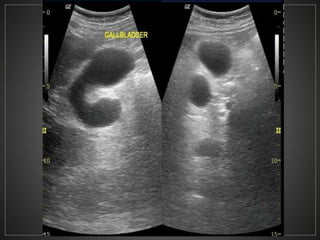

• #20 Magnificacion de USG en escala de grises donde se observa vesicula biliar distendida, con multiples septos internos algunos parciales y otros completos, sin aparentes litos en su interior, en relacion a vesicula septada.

• #21 Colangio RM VB multiseptada sin anomalias de la via biliar .